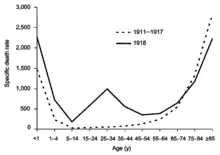

The most famous and lethal outbreak was the 1918 flu pandemic (Spanish flu) (type A influenza, H1N1 subtype), which lasted into 1920. It is not known exactly how many it killed, but estimates range from 17 million to 100 million people.[15][201][216][217] This pandemic has been described as "the greatest medical holocaust in history" and may have killed as many people as the Black Death.[199] This huge death toll was caused by an extremely high infection rate of up to 50% and the extreme severity of the symptoms, suspected to be caused by cytokine storms.[217] Symptoms in 1918 were so unusual that initially influenza was misdiagnosed as dengue, cholera, or typhoid. One observer wrote, "One of the most striking of the complications was hemorrhage from mucous membranes, especially from the nose, stomach, and intestine. Bleeding from the ears and petechial hemorrhages in the skin also occurred."[216] The majority of deaths were from bacterial pneumonia, a secondary infection caused by influenza, but the virus also killed people directly, causing massive hemorrhages and edema in the lung.[218]

The 1918 flu pandemic was truly global, spreading even to the Arctic and remote Pacific islands. The unusually severe disease killed between two and twenty percent of those infected, as opposed to the more usual flu epidemic mortality rate of 0.1%.[201][216] Another unusual feature of this pandemic was that it mostly killed young adults, with 99% of pandemic influenza deaths occurring in people under 65, and more than half in young adults 20 to 40 years old.[219] This is unusual since influenza is normally most deadly to the very young (under age 2) and the very old (over age 70). The total mortality of the 1918–1919 pandemic is not known, but it is estimated that 2.5% to 5% of the world's population was killed. As many as 25 million may have been killed in the first 25 weeks; in contrast, HIV/AIDS has killed 25 million in its first 25 years.[216]